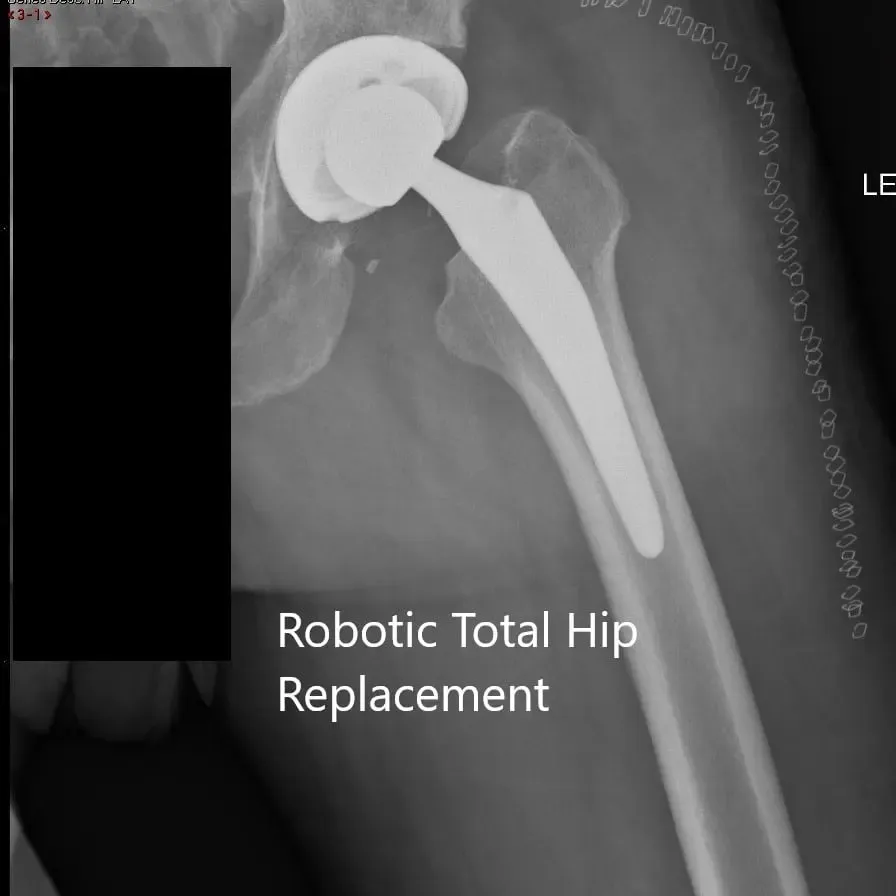

OPERATION: Robotic left total hip arthroplasty.

IMPLANTS USED: Acetabular shell 62 mm with 10-degree poly 36 mm with 127-degree neck stem size 6 with a ceramic head, 36-mm +O.

Postoperative X-ray of the left hip showing the AP and lateral views.